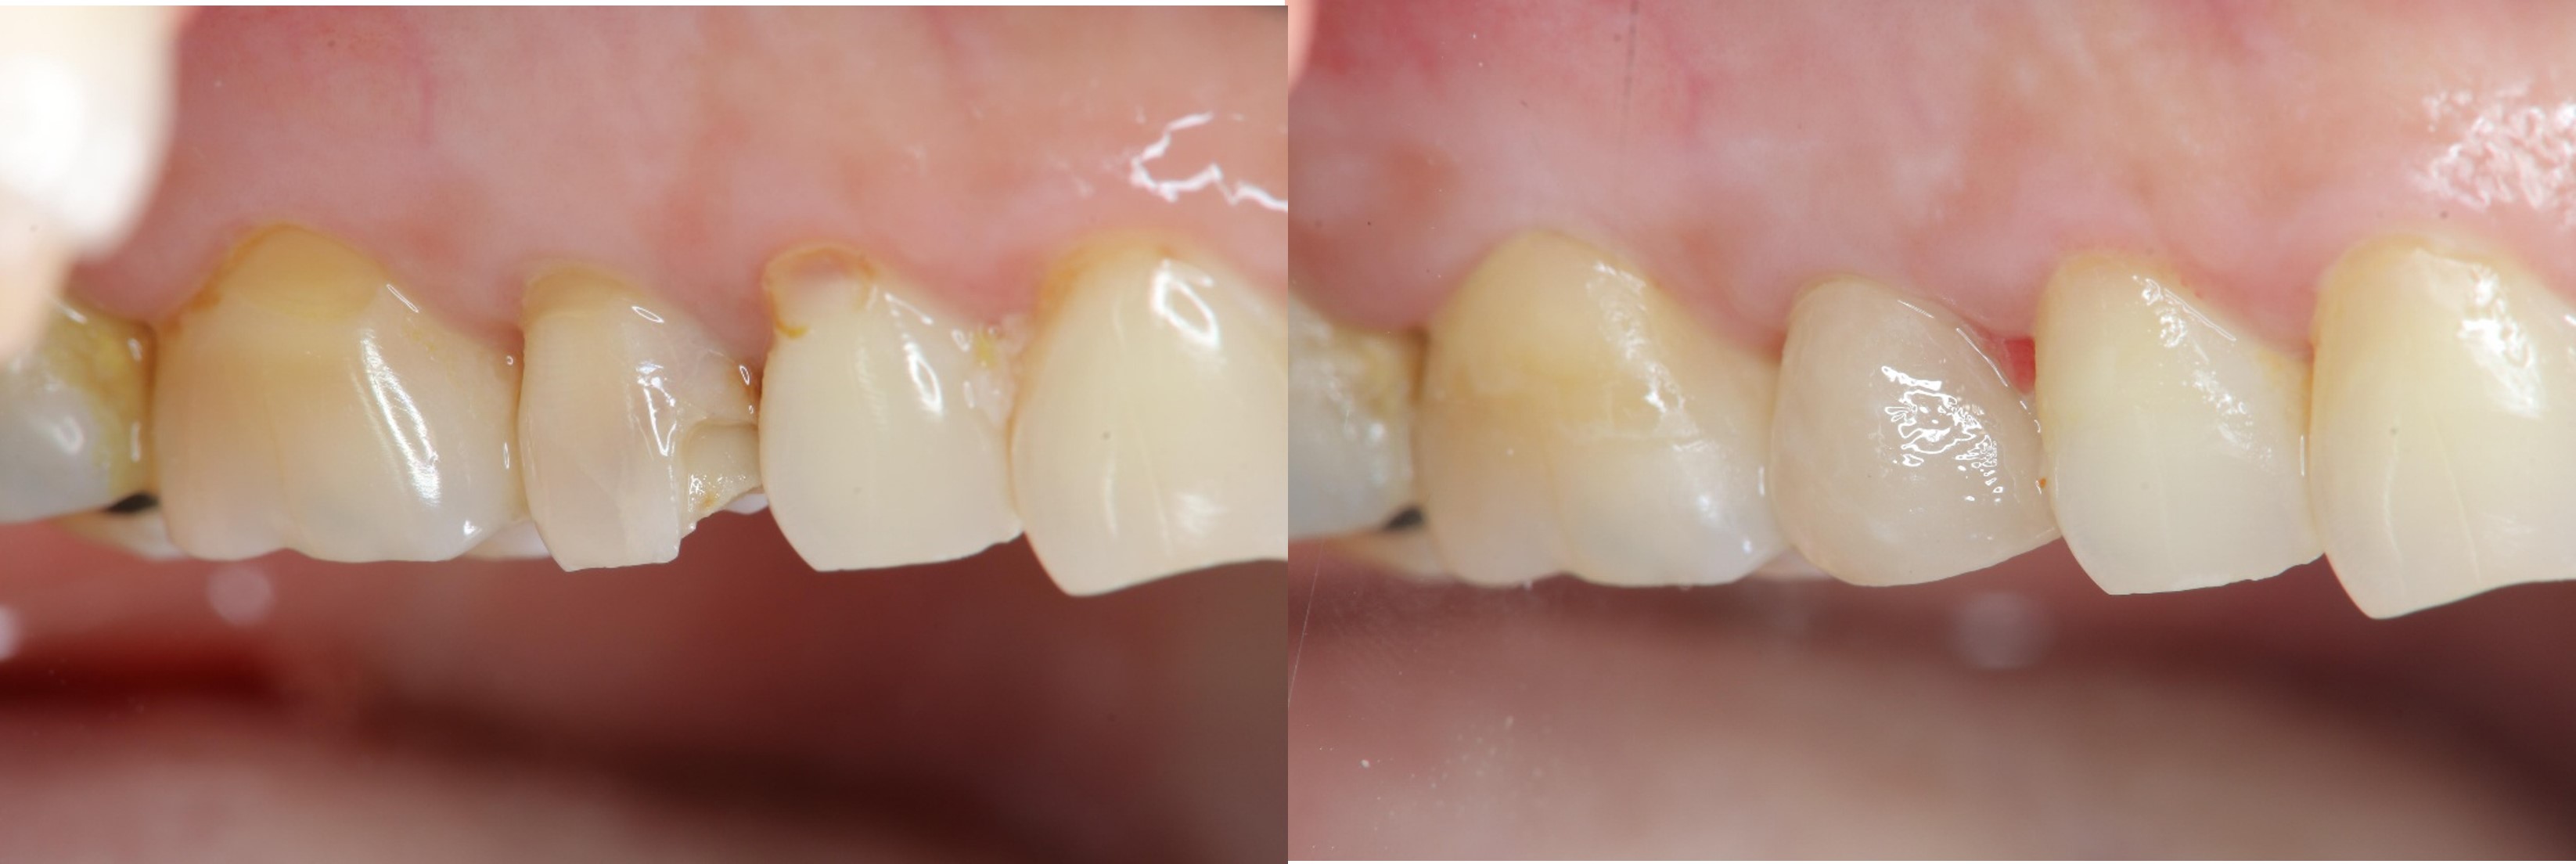

術前、術後比較

當蛀牙破壞程度大,陶瓷冠塊體是根據蛀牙的窩洞量身訂做,不管是顏色、精密度都是最佳的選擇,因此是非常美觀與持久的填補窩洞材料與技術